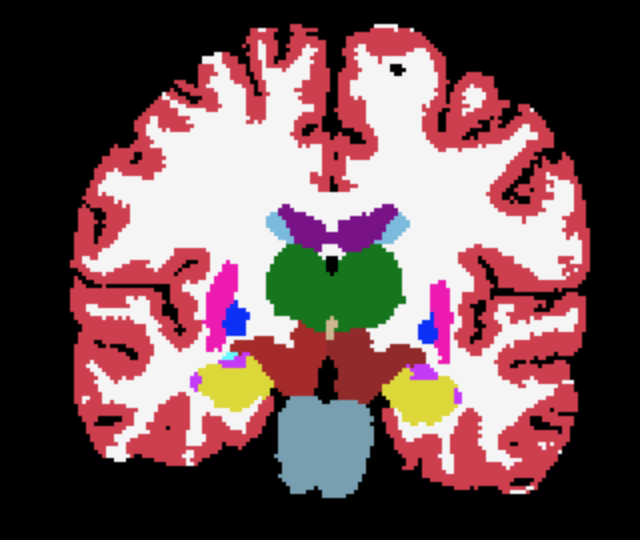

where and are the ground-truth and transformed segmentations respectively, and the Dice loss is now computed over multiple neuroanatomical structures (see Figure 1 for an example segmentation).

The overall training framework of the network is illustrated in Figure 1. Given an input scan, the network regresses both the coordinate means and the standard deviations , as well as a foreground mask . The optional atlas segmentation loss is denoted by the dashed box.

Third-level uncertainty: uncertainty at downstream tasks. To illustrate how the uncertainty could be used in a downstream task we show samples of atlas deformations and associated propagated segmentations in Figures 5 and 6. Both figures highlight the variability of the samples, which would have a direct effect on any downstream analysis using quantities extracted from the segmentations, e.g., regional volume (Desikan et al., 2009). The sample-to-sample differences, along with the variance, are again concentrated on the cortex. This registration-based uncertainty, when not accounted for, can decrease the power of downstream statistical analyses, or be mistaken for aging effects if the registration errors correlate with age.